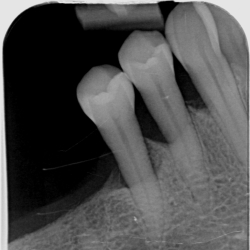

• Røntgenanalyse og vurdering af sygdomsprogression